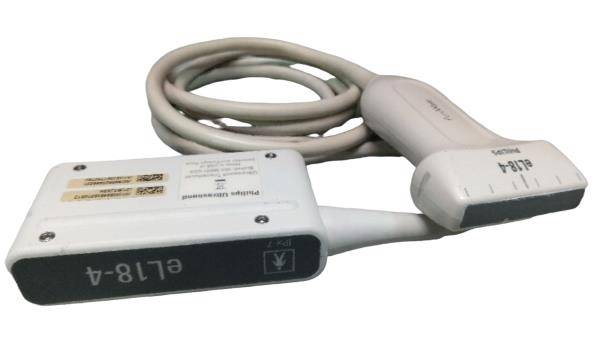

The Sonosite M-Turbo Portable is compatible with a wide range of probes and transducers, enhancing its versatility across various medical disciplines. Whether it's for abdominal imaging, vascular assessments, or musculoskeletal evaluations, this ultrasound machine delivers precise and dependable images. Moreover, the device supports advanced imaging modes such as Color Doppler, M-Mode, and Power Doppler, providing comprehensive diagnostic options for practitioners.